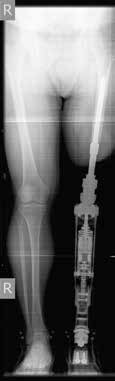

Bei der Durchführung des Indikationsverfahrens wird von den Autoren ein multidisziplinärer Teamansatz verfolgt. Das Behandlungsteam für die Osseointegration besteht aus einem orthopädischen Chirurgen, einem Fallmanager, einem Rehabilitationsmediziner und einem Physiotherapeuten. Patienten, die zur Implantation einer knochenverankerten Prothese überwiesen werden, werden vom Fallmanager in eine ambulante Gruppenklinik eingeladen. Vor ihrem Besuch füllen sie den Fragebogen für Personen mit einer transfemoralen Amputation (Q‑TFA) aus 1. In der ambulanten Gruppenklinik wird zunächst eine radiologische Untersuchung des verbleibenden Femurs bzw. der verbleibenden Tibia durchgeführt und eine kalibrierte Gesamtansicht der beiden unteren Extremitäten angefertigt (Abb. 1a). Bei Patienten mit Unterschenkelamputation oder mit kurzem Oberschenkelstumpf wird ein CT-Scan durchgeführt. Mit diesem CT-Scan werden die Größe und das Design des anzufertigenden kundenspezifischen Implantats ermittelt. Sämtliche Einzelheiten der Behandlung werden im Rahmen einer Plenarsitzung vom Chirurgen und vom Rehabilitationsmediziner vorgestellt, gefolgt von Einzelberatungen mit dem gesamten Osseointegrationsteam. Während der Einzelgespräche werden dem Rest der Kandidaten und ihren Angehörigen zwei Personen mit knochenverankerter Prothese vorgestellt, die ihre Rehabilitation erfolgreich abgeschlossen haben. Diese berichten den neuen Kandidaten von ihren Erfahrungen und zeigen ihnen ihre knochenverankerte Prothese. Abschließend wird ein gemeinsamer Konsens in Bezug auf die Indikation zur Behandlung auf Grundlage der Ein- und Ausschlusskriterien 2, der Krankengeschichte, der körperlichen Untersuchung, der Q‑TFA-Ergebnisse sowie der Radiographie erzielt. Kandidaten mit unrealistischen Erwartungen an ihre zukünftige Funktionsfähigkeit mit einer knochenverankerten Prothese werden an die klinischen Psychologen zum Gespräch überwiesen, um ihre Erwartungen zu korrigieren, die wahrscheinlich zu hoch sind.